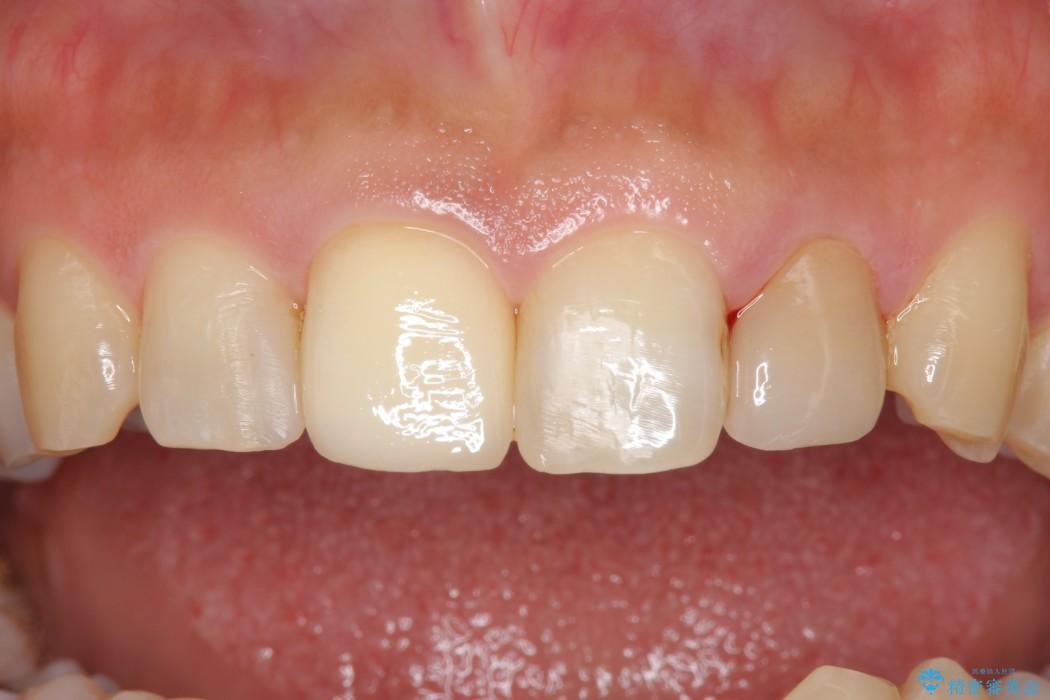

治療後について

今回のケースでは丁寧に虫歯を取りきることにより、神経を保存することができました。